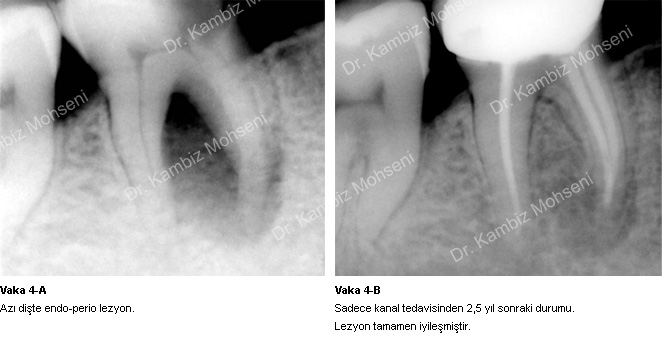

İltihabın sebebi kök kanal sistemindeki mikroorganizmalardır. Uygun bir kanal tedavisi ile ortam mikroorganizmalardan arındırılırsa iltihabın iyileşme şansı oldukça yüksektir. Bu konuyla ilgili örnek vakaları inceleyebilirsiniz;

Vaka 2-A, 2-B, 4-A, 4-B ve 5-A, 5-B.